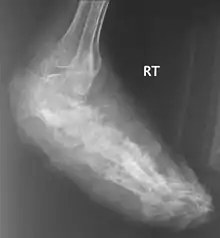

В костях через надкостницу масса зерен постепенно может переходить в костную ткань и костный мозг, и иногда в таких случается спонтанный патологический перелом. Рентгенологическое исследование определяет множественные остеомиелитические поражения, которое можно описать как полости и периостальные образования новой костной ткани. Также иногда наблюдают остеопороз, вызываемый давлением окружающих отечных тканей и атрофию. Вследствие хронического периостального фиброза суставы иногда тугоподвижны. При мицетомах черепа наблюдали диффузное истончение костей, вызванное давлением кожных образований и иногда трабекулы, в некоторых местах, хотя и очень редко, могут быть и небольшие области остеолиза.

Для диагностики мицетомы обычно используют рентгеновские снимки, УЗИ, аспирационную пункционную биопсию. Выбор метода зависит от выделения возбудителя и эндемических мест инфекции.